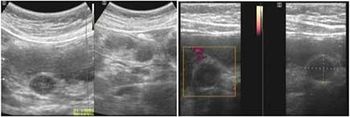

Case History: A 57-year-old woman presented complaining of a long lasting epigastric pain. The pain was irregular, vague without spreading or progression or correlation to alimentary habit.